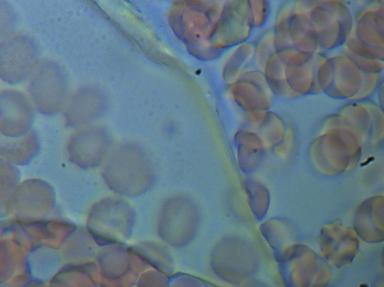

1.RULONIZACJA I AGREGACJA ERYTROCYTÓW

To poważne zagrożenie zatorowo - zakrzepowe, co klinicznie może spowodować zapalenie naczyń obwodowych, zawał serca, udar mózgu a nawet nagły zgon. Agregacji i rulonizacji nie można stwierdzić tradycyjnymi badaniami diagnostycznymi.